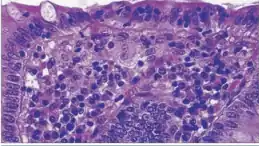

A micrograph demonstrating cryptitis, a microscopic correlate of colitis. H&E stain.

An important investigation in the assessment of colitis is biopsy. A very small piece of tissue (usually about 2mm) is removed from the bowel mucosa during endoscopy and examined under the microscope by a histopathologist. It can provide important information regarding the cause of the disease and the extent of bowel damage.